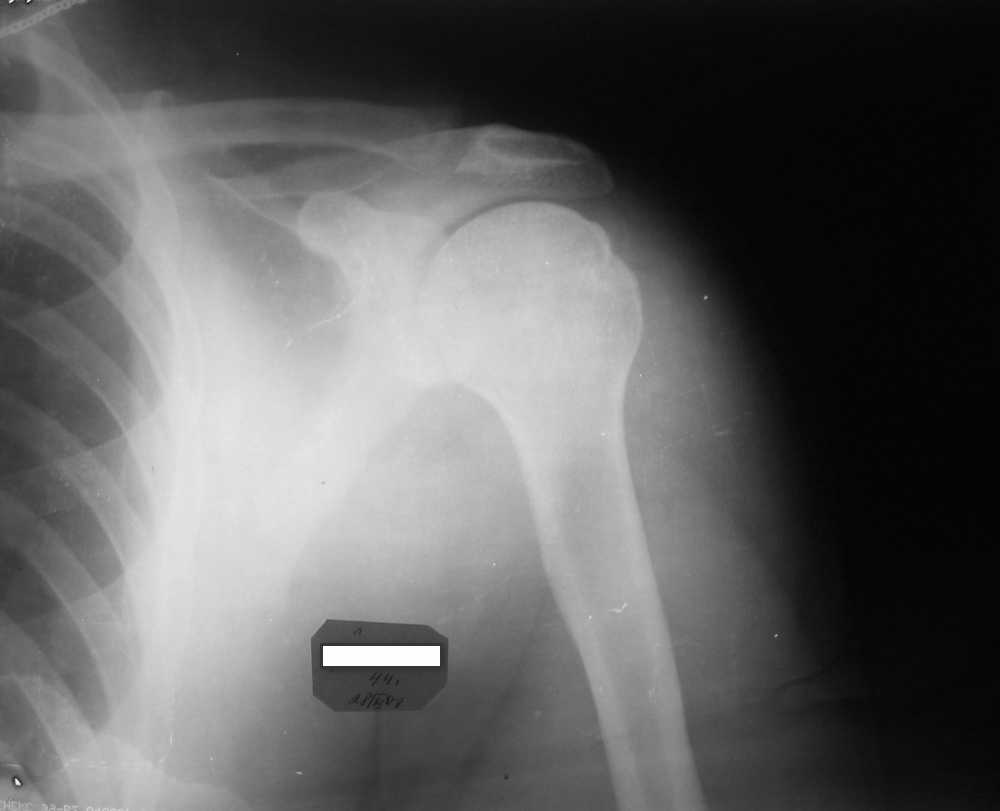

Отправлено Олег Бейдик 28 Ноябрь 2007, 23:25

Мужчина, 45 лет. Профессионально занимается культуризмом. При жиме лёжа возникают резкие боли в левом ключично-акромиальном сочленении в течение 3 лет. В покое болей нет. Похожая картина была и справа, однако удалось стабилизировать ситуацию с помощью консервативоного лечения.Что, на Ваш взгляд, следует предпринять? Какие дополнительные исследования были бы полезны для определения тактики? Нет ли здесь показаний к декомпрессии подакромиального пространства? Если да, то что именно сделать?

Судя по снимкам, у вашего пациента артрит АС сустава.

сделайте тест с лидокаином внутри суставно - если боли купируются при выполнении нагрузок, то АС резекция 0,6-0,8 см решит проблему. Если боли не

уходят, и вы при осмотре сустава находите симптомы субакромиального импинджмента, попросите рентгенологов косую проекцию(Neer's view).